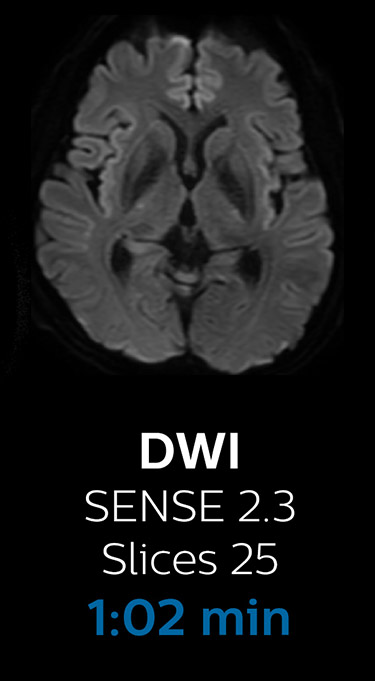

With Compressed SENSE, the scan time for the routine brain examination at KNC was reduced from 15:48 to 10:19 minutes, which corresponds to 35% reduction.

Brain with Compressed SENSE

Ingenia 3.0T CX

Scan time 10:19 min.